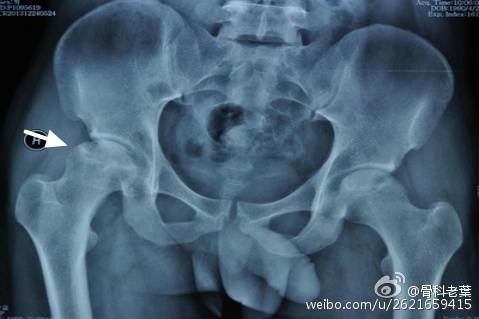

III期 磁共振出现异常,X线片显示软骨下塌陷(新月征),股骨头内出现空洞,股骨头没有变扁

II期和III期的患者治疗方法相同,因为此时股骨头虽然还没有变形,暂时还不需要行人工关节置换术,但是股骨头已经出现空洞,随时股骨头就会塌陷变形,所以单纯的股骨头减压术是不能达到治疗效果的。这时就需要在股骨头减压的同时,植入一根支撑棒,顶住股骨头空洞区,防止股骨头在负重的情况下过早塌陷。其他治疗同之前相同,口服以上药物,定期复查,密切观察病情发展,尽量避免重体力劳动和爬山爬楼。